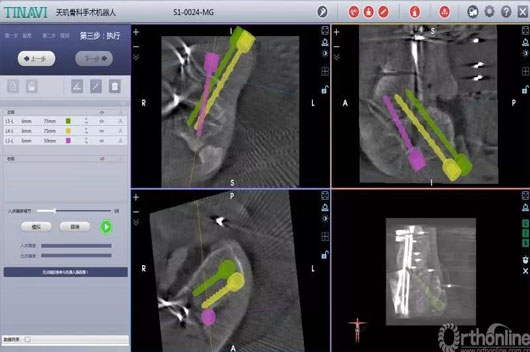

这两台手术划分是机械人辅助后踝骨折闭合复位空心钉牢靠术和机械人辅助距下枢纽融合术。。。。。。。特殊是机械人辅助距下枢纽融合术,,,,,敌手术的精准度要求很是高。。。。。。。

古板手术要领需要大面积袒露患部,,,,,导针重复操作确定位置、同时多次透视,,,,,手术时间长、患者损伤大,,,,,并发症几率高。。。。。。。而现在只需要把融合的枢纽面举行处置惩罚后,,,,,装置好骨科导航机械人,,,,,把伤口用敷料盖好后,,,,,在病人体外用机械人做妄想,,,,,并凭证妄想精准置入螺钉。。。。。。。病人真正的手术时间大大缩短,,,,,袒露的伤口小、辐射少、手术效果抵达最佳。。。。。。。

术中妄想螺钉位置

术中妄想后踝螺钉位置

术中妄想远端锁钉位置